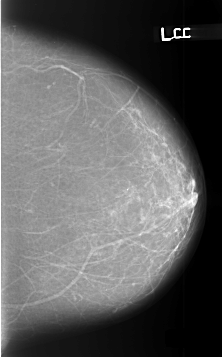

Digital Database for Screening Mammography

Volume: benign_13 Case: B-3443-1

B_3443_1.LEFT_CC

LEFT_CC LINES 5712 PIXELS_PER_LINE 3544 BITS_PER_PIXEL 12 RESOLUTION 50 NON_OVERLAY

LEFT_MLO LINES 5720 PIXELS_PER_LINE 3704 BITS_PER_PIXEL 12 RESOLUTION 50 NON_OVERLAY